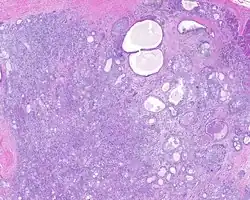

Low power H&E stained image of parotid gland sclerosing polycystic adenoma

When reviewed by a pathologist, the findings are quite similar to fibrocystic changes of the breast, although they are different enough, that it is now recognized to actually represent a true neoplasm (clonal proliferation) through various studies.[5] Specifically, the lesions are usually well-circumscribed, containing lobules of haphazardly arranged ducts, myoepithelial cells, and acini that have abundant sclerosing or hyalinized fibrosis. Apocrine change is quite common in the ductal cells.[6] The ducts range from small ductules to cystically dilated spaces (more than 4 striated duct-widths across), often containing products of secretion or reactive histiocytes. A very curious and characteristic finding in all of the lesions is the presence of bright pink (eosinophilic) acinar granules (which are altered zymogen).